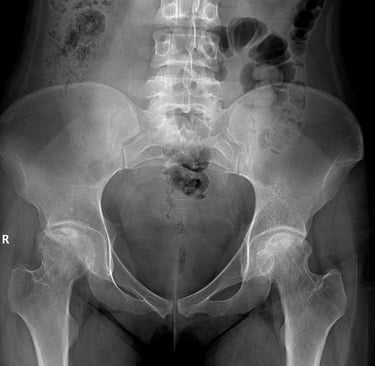

Düz Röntgen (Erken Evre X-Ray) Sens. %15 - 25 Spe. %90+ LR+ 1.5 LR- 0.85

Erken evrede negatif çıkması hastalığı ekarte ettirmez (körlüktür). Sadece geç evre çöküşü gösterir.

3. Radyolojik Evreleme ve "Geri Dönüşü Olmayan Nokta" Analizi

Görüntüleme bir fotoğraf değil, bir zaman çizelgesidir. Amacımız subkondral çökmenin (Point of No Return) ne zaman gerçekleşeceğini öngörmektir.

Evre 0: Röntgen ve MR normal. Semptom yok / Şüphe. (LR+ = 1.0)

Evre I: Röntgen normal, MR pozitif (Çift Çizgi). Hafif ağrı. (LR+ 15.0 - Tanı kesin)

Evre II: Skleroz, kistik değişiklikler. Belirgin ağrı. (LR+ 10.0 - Röntgen tanısaldır)

Evre III: Crescent Sign (Hilal Belirtisi). Şiddetli ağrı, subkondral kırık ve çökme başlar. (LR+ - ∞ - Biyomekanik iflas)

Evre IV: Eklem aralığında daralma, ileri osteoartrit. Terminal safha.